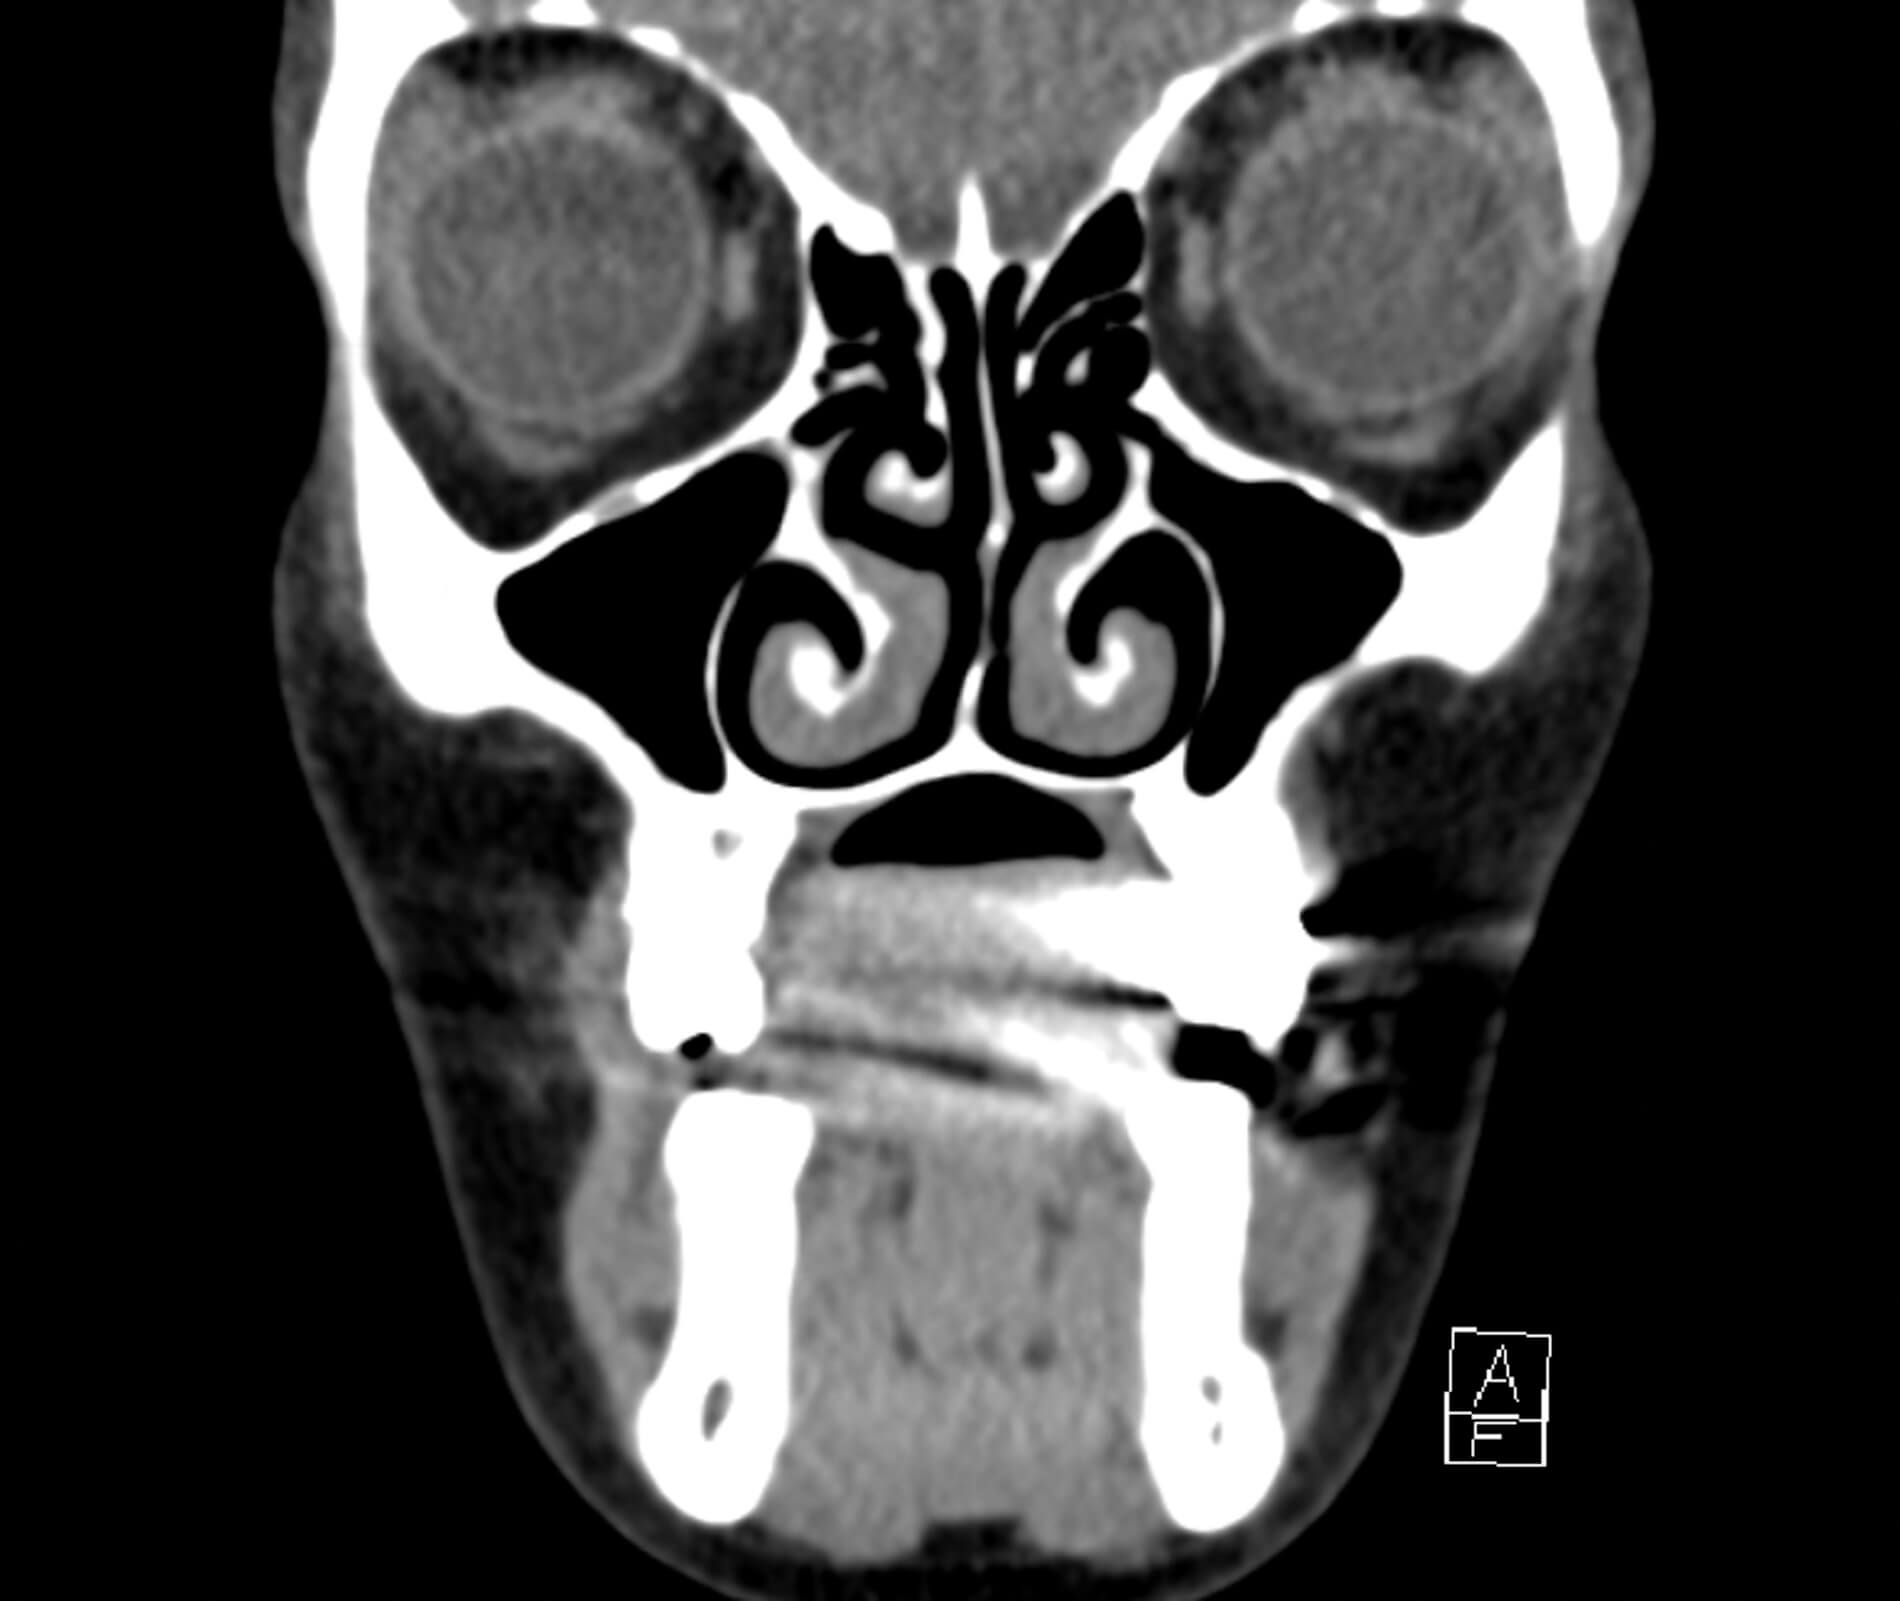

Figure 1a: CT facial bones, brain, sinuses without contrast - thick, soft.

Computed tomography (CT) imaging showed no acute intracranial abnormality with minimal periorbital haemorrhage without evidence of significant optic nerve compression. Despite this, clinical findings strongly indicated OCS, prompting the decision to proceed with an emergency LCC.